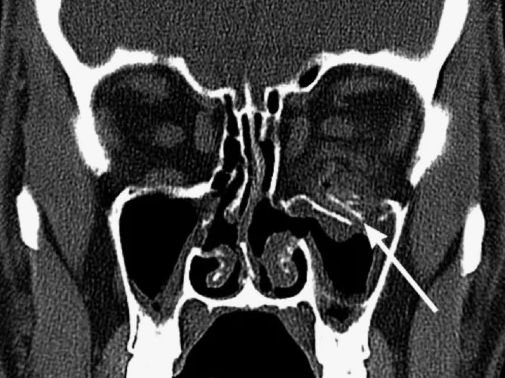

Магнитно-резонансная томография (МРТ):один из самых эффективных методов диагностики заболеваний